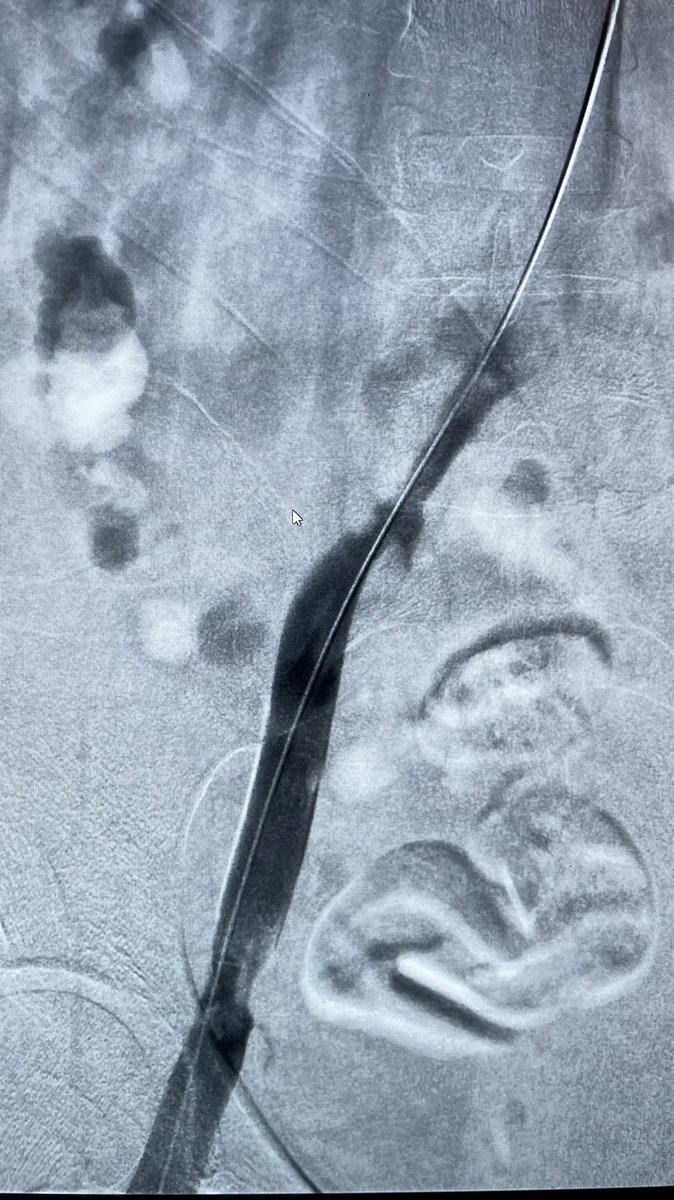

Case 62: with @BhaveshPopat7 . Right lower limb acute extensive iliofem DVT; pharmacomechanical thrombectomy with Angiojet; images below 👇 . #MedTwitter #meded #hematology @SIRRFS @SIR_ECS @SIRspecialists @nihardesai7

Iliac occlusion crossed - felt to be acute on chronic. Angiojet pulse spray 10mg in 100ml Angiojet thrombectomy 100s Iliac thrombus cleared and underlying stenosis identified. 10mm X 8cm bare metal stent deployed. TPA infusion left for SFA and pop thrombus